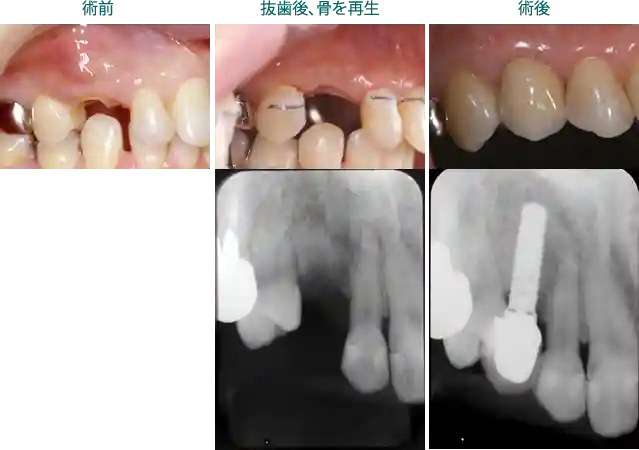

ケーススタディ1:抜歯後、骨の造成をし、インプラントを埋入した患者様

このケースは歯根が破折したため抜歯となりました。破折して時間が経過すると炎症も持続しますので、骨の吸収量が多くなります。抜歯する時期も重要です。

このケースでは、抜歯時期が適当であったため、少量の骨の造成で済みました。

骨造成には造成量により別途費用(¥121,000【税込】~)がかかります。

① 費用:¥479,600【税込】~

②リスク:骨質によりインプラントは出来ないことがあります。また、骨の造成ができない場合、インプラントは適応になりません。チタンアレルギーのある方には使用できません。